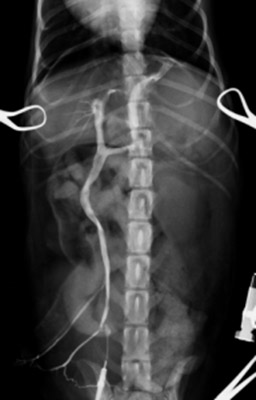

まず開腹下にて門脈造影検査と言われる特殊な血管造影検査を行い、シャント血管とレントゲン検査にて探します。CT検査と同様にシャント血管が左胃静脈-左横隔膜静脈のシャント血管が確認できました。

左胃静脈-横隔膜静脈を介した門脈-後大静脈シャント。